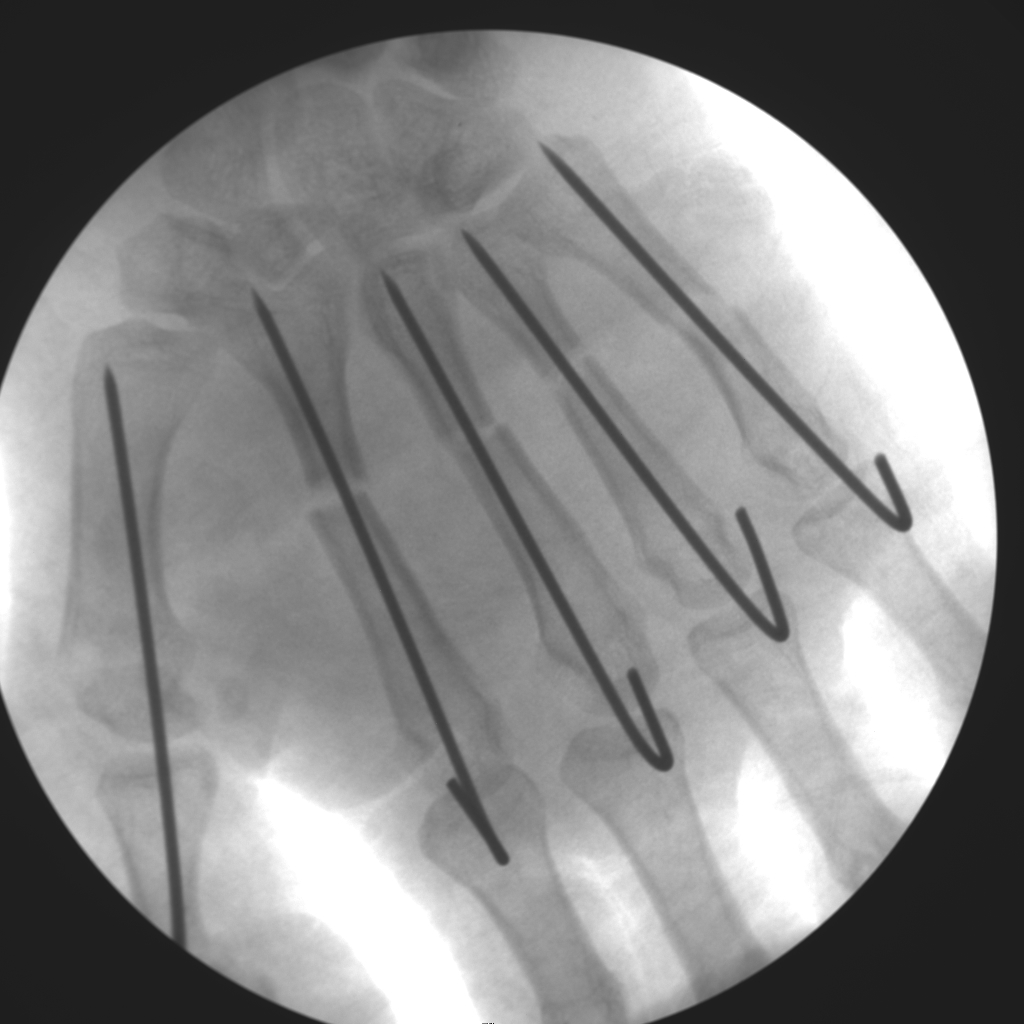

Skan-C plays a critical role in orthopaedic procedures, providing excellent imaging during interventional procedures, and allowing for precise localization and accurate treatment. The ability of Skan-C to offer dynamic visualization of visualization structures enhances patient safety, minimizes complications, and improves the overall effectiveness of orthopedic interventions.

CRIF - Closed reduction internal fixation

ORIF - Open reduction internal fixation

High-quality imaging

Skan-C uses advanced imaging technology, such as pulsed fluoroscopy and digital subtraction angiography, to provide highly detailed images of the affected area. This allows doctors to perform procedures with increased precision and accuracy, and better patient outcome